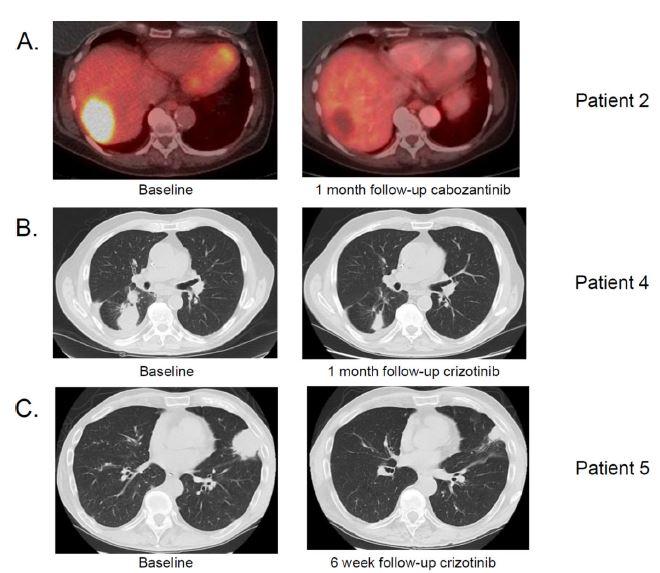

靶向治疗方面,2015年美国纽约纪念斯隆凯特琳癌症中心的Paul K. Paik教授率先报道了4例利用克唑替尼或卡博替尼治疗晚期MET基因14号外显子突变的肺癌患者的成功案例。

其中一例患者接受治疗后肿瘤完全消失,其余病人肿瘤明显缩小。下图展示了几位病人治疗前后的影像学片子,从中可见肿瘤代谢活性消失、肿瘤大小明显缩小。